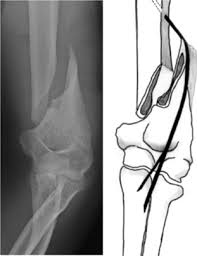

Spiral fractures are usually the result of high energy trauma and are likely to be associated with. Summary summary (text) medline pmcid list. A fracture, sometimes called a torsion fracture, in which a bone has been twisted apart. Spiral fractures often occur when the body is in motion while one extremity is planted. Spiral fracture — sagittarius a star 03:25. Detailed step by step desription of intramedullary nailing for simple fracture, spiral located in our module intramedullary fixation is valuable and appropriate for the majority of tibial fractures. Two spiral fractures sustained following only minor trauma. Meaning of spiral fracture medical term.

Two spiral fractures sustained following only minor trauma. Complete fractures are categorized based on the way the bone breaks. It occurs due to a rotational, or twisting, force. Try our newest study sets that focus on spiral fracture to increase your studying efficiency and retention. Detailed step by step desription of intramedullary nailing for simple fracture, spiral located in our module intramedullary fixation is valuable and appropriate for the majority of tibial fractures. Other articles where spiral fracture is discussed: A spiral fracture is a bone fracture occurring when torque is applied along the axis of a bone.1 spiral fractures often occur when the body is in motion while one extremity is planted. Spiral fracture femur (there is a significantly displaced spiral fracture of the proximal femoral. A spiral fracture, also known as torsion fracture, is a type of complete fracture. A spiral fracture is a bone fracture caused by a twisting force. A spiral fracture is usually treated right away with surgery. Summary summary (text) medline pmcid list. Know ways to lower your risks in the first place.

A fracture, sometimes called a torsion fracture, in which a bone has been twisted apart. Shiel jr., md, facp, facr. A spiral fracture is a bone fracture occurring when torque is applied along the axis of a bone. Other articles where spiral fracture is discussed: Summary summary (text) medline pmcid list. It occurs due to a rotational, or twisting, force. Detailed step by step desription of intramedullary nailing for simple fracture, spiral located in our module intramedullary fixation is valuable and appropriate for the majority of tibial fractures. Also called a torsion fracture, a spiral my son suffered a spiral femur fracture and the er doctor didn't report it.

Spiral fracture femur (there is a significantly displaced spiral fracture of the proximal femoral. A spiral fracture is usually treated right away with surgery. Summary summary (text) medline pmcid list. A spiral fracture is a bone fracture that occurs when a long bone is broken by a twisting force. Also called a torsion fracture, a spiral my son suffered a spiral femur fracture and the er doctor didn't report it. It occurs due to a rotational, or twisting, force. Detailed step by step desription of intramedullary nailing for simple fracture, spiral located in our module intramedullary fixation is valuable and appropriate for the majority of tibial fractures. Medical definition of spiral fracture. Spiral fractures are complete fractures of long bones that result from a rotational force applied to the figure 1. Spiral fractures are usually the result of high energy trauma and are likely to be associated with. Try our newest study sets that focus on spiral fracture to increase your studying efficiency and retention. Bone depressed fracture fractures simple fracture closed reduction. Finally, two days later, the other.